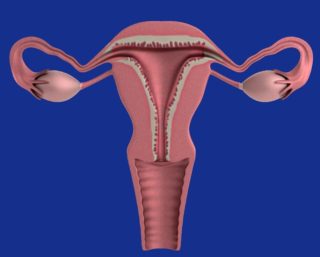

Ashermanův syndrom je charakterizovaný jako poškození bazální vrstvy děložní sliznice (endometria) po zákrocích, např. po revizi dělohy po potratu, po odstranění myomů aj. Pacientky mívají